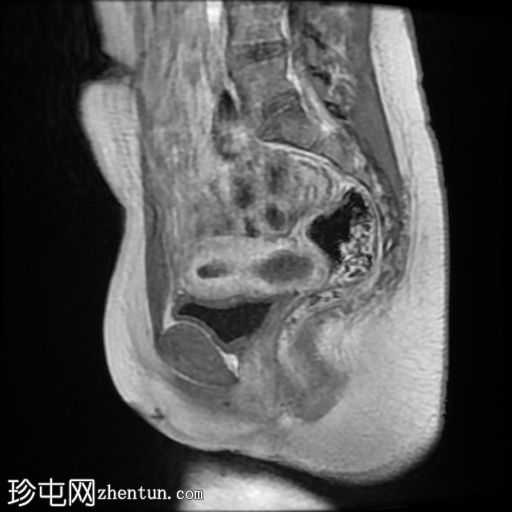

矢状面

T2

子宫体相对较小,发育良好。宫颈发育不全。

阴道整体不显影,远端可见一层细小的纤维组织,在轴向和矢状面T2加权序列上最为明显。

随后,子宫内膜和宫颈腔扩张,出现混合液体/血液降解信号(积血)。它诱发中至高T1信号,伴有依赖性低信号碎片,无病理性强化。

周围轻度盆腔积液,盆腔及附件脂肪平面模糊,信号相似,增强后强化明显。这些发现提示可能有渗漏液/血液积聚,并伴有腹膜反应。

本例患者在青春期出现慢性钝痛和原发性闭经。我们观察到宫颈阴道交界处生殖道流出道梗阻、子宫积血、轻度出血性腹水积聚以及腹膜反应。